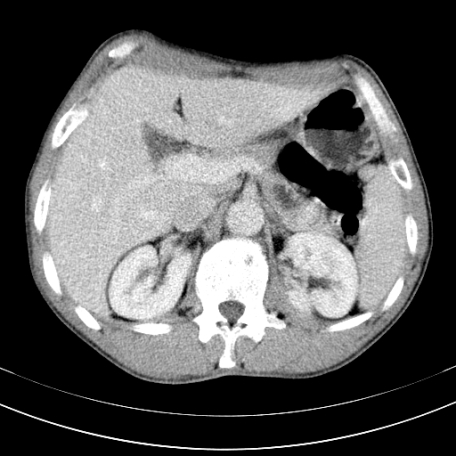

标题: CT21441:男55岁,上腹部胀痛半年余,请老师们看看是后腹膜淋巴 [打印本页]

标题: CT21441:男55岁,上腹部胀痛半年余,请老师们看看是后腹膜淋巴

腹主动脉右侧有一个,有肿瘤病史吗?

腹膜后淋巴结肿大,原因待查。